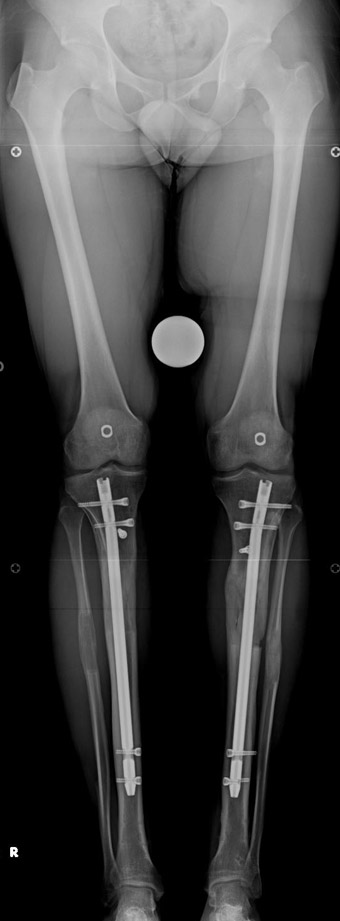

Postoperative care: Distraction is commenced at day 10. 0,25 mm of lengthening is perfomed 4 times daily (every 6 hours). Hip and knee joint motion exercises begin at 1-2. day postoperatively. For many years, the treatment of lower extremity shortness has been very hard for the patient and the surgeon. The techniques developed after the introduction of Ilizarov’s distraction osteogenesis concept have pioneered a new era, and have been considered to be procedures in which previous complications are encountered much less frequently.

In selected cases, we prefer to use a combination of a unilateral dynamic axial fixator and an interlocked intramedullary nail, in order to protect the length and alignment after the completion of the lengthening procedure. As a prerequisite for this technique, the narowest diameter of the medullary cavity shall be wider than 7 mm and the length of the nail segment distal to the osteotomy site shall be at least 8 cm. after the completion of the lengthening procedure.The intramedullary nail neutralizes shear and bending forces on femur during lengthening, shortens external fixation time, and protects newly formed bone against fractures. In our series, subtrochanteric osteotomy was performed in one case. No varus angulation occured despite the intramedullary nail.

The combination of intramedullary anil and dynamic axial external fixator is harder as a technique than Standard Ilizarov applications. However, it is stil appealing due to the following advantages: shortening of the duration of external fixation, protection against refracture, early rehabilitation, gaining maximum range of motion and daily quality of life. These advantages are more important than disadvantages such as increased cost, increased blood loss and potetntial deep infection. All in all, we believe that the technique of femoral lengthening over an intramedullary nail is a safe and reliable method and provides advantages over standard Ilizarov aplications.